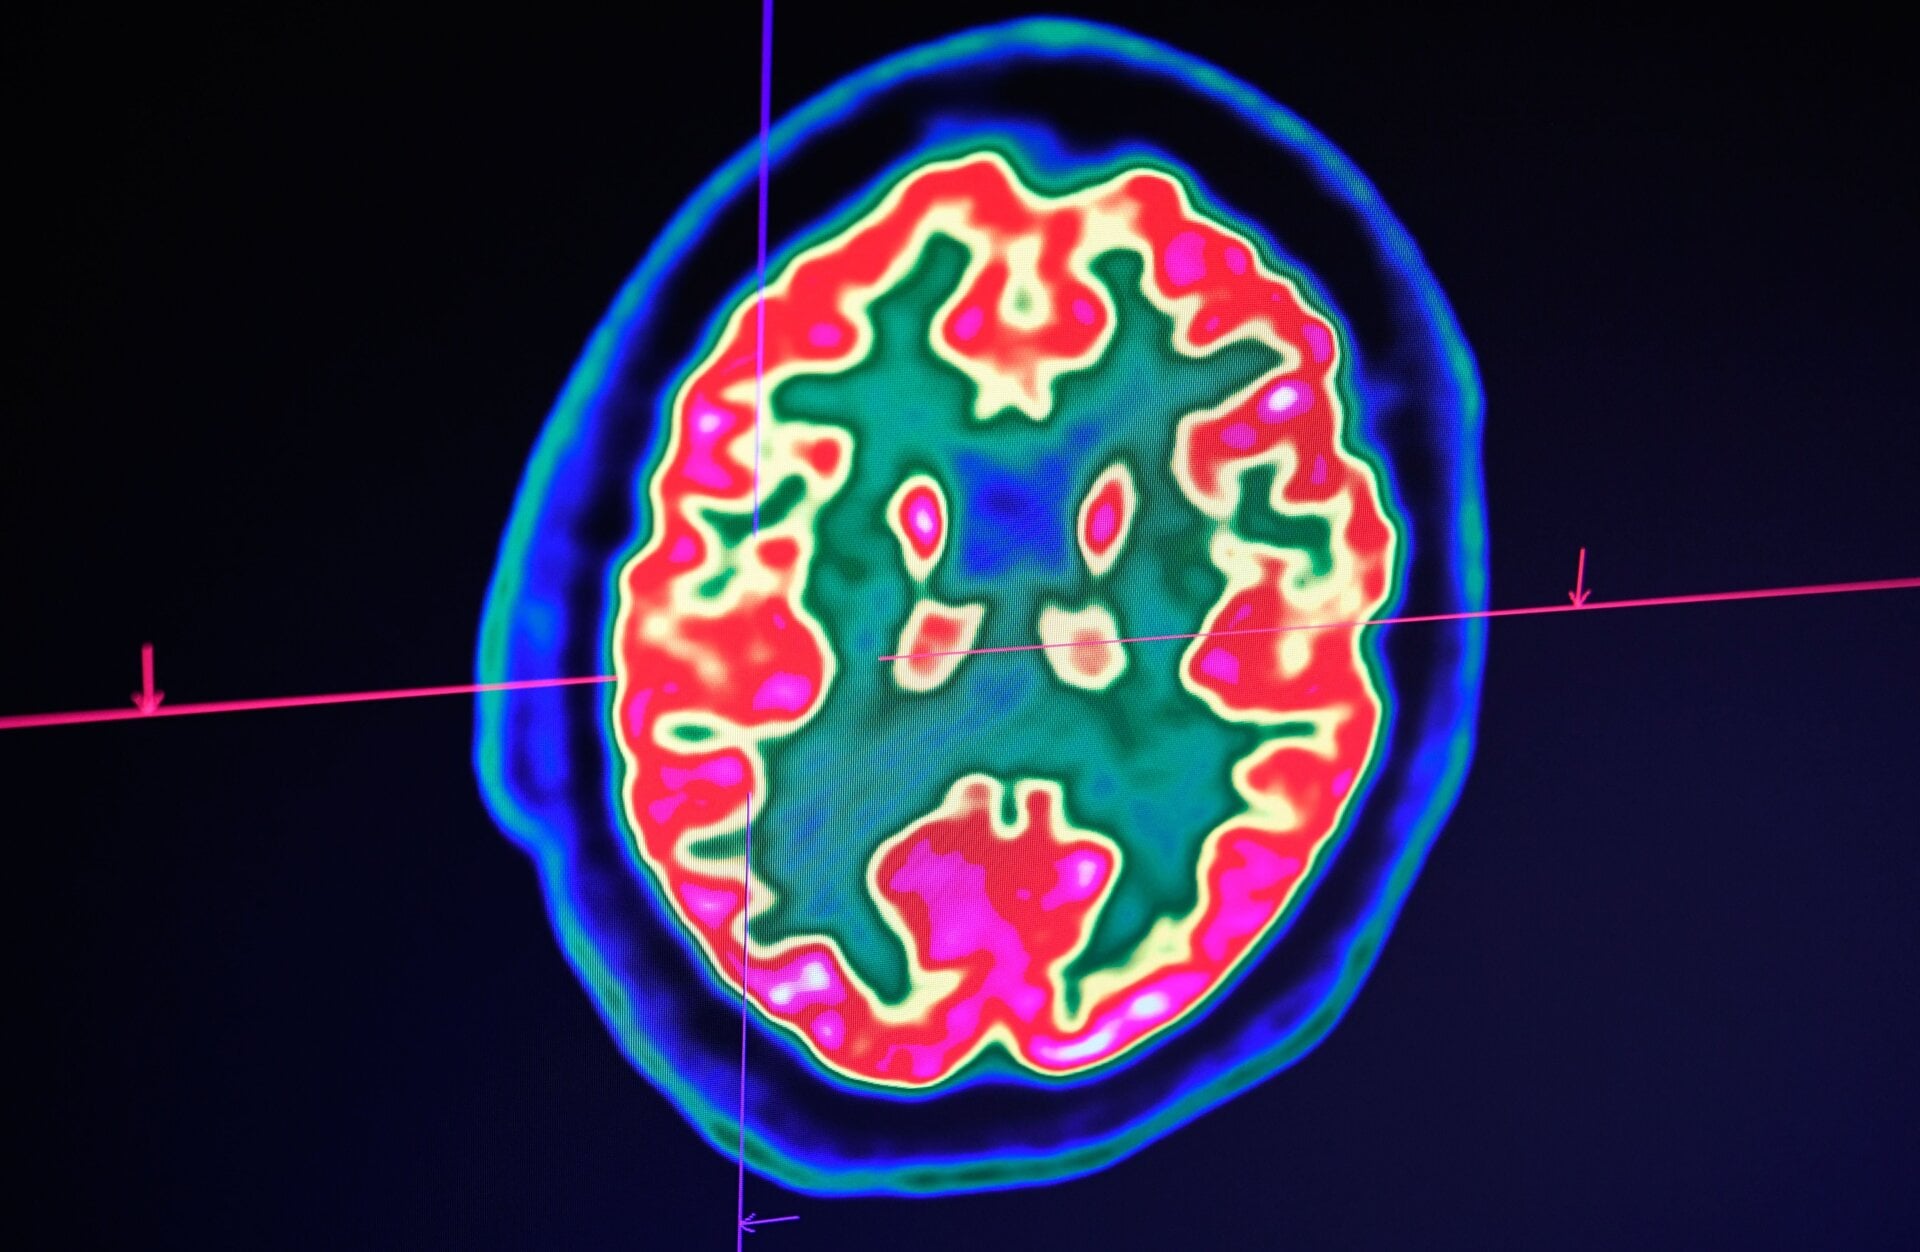

The authors studied the cases of 43 people with confirmed or suspected covid-19 who were referred to a large hospital in the UK that specializes in neurological problems. The patients were between the ages of 16 and 85 and ranged in the severity of their other covid-19 symptoms. Their neurological symptoms included delirium (a period of severe mental confusion that often arrives rapidly), psychosis, stroke, seizures, and face or limb muscle weakness, among others. In brain scans, there was evidence of swelling, hemorrhaging, and other damage to various parts of the brain.

Many of the cases also developed a rare condition known as acute demyelinating encephalomyelitis, or ADEM. ADEM is characterized by a brief but potent burst of inflammation that attacks the outer layer of myelin that surrounds nerve fibers. While some neurological symptoms did appear more frequently in people with severe respiratory covid-19, severity didn’t predict the odds of getting ADEM in these cases. Even relatively mild cases of covid-19 led to frightening episodes of neurological illness.